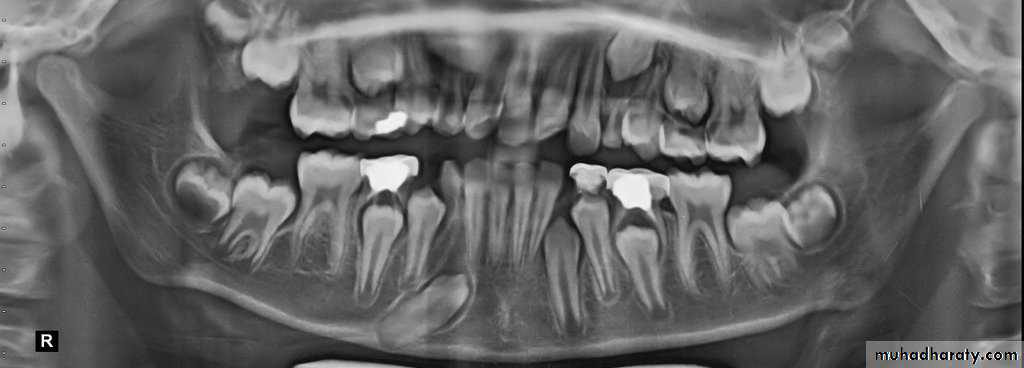

Impacted lower premolars

It occurs mostly due to loss of space by drifting forward of the first permanent molar after early extraction of the second deciduous molar, other causes are gross malformation and retention of the deciduous predecessor.Localization is by periapical film or OPG with occlusal view to demonstrate the bucco-lingual position.

Removal is by raising a 2-sided or 3-sided buccal flap, with preservation of the mental nerve, bone removal, sectioning of the tooth if needed and extraction of the tooth. In young patients it is essential to consult an orthodontist before extraction.